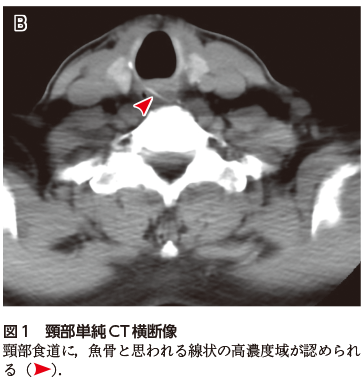

• A1:頸部食道内に線状の高濃度域が認められる(図1図2).形態や濃度からは魚骨と考えられる.

高齢者が誤飲する異物として,魚骨のほか,PTPシート(薬剤の包装)や義歯が有名である.いずれのケースも,疑われた場合はその有無および位置を確認するためにCTが施行されることが多い.魚骨は一般的にCTで線状の高濃度域として描出される.一方,誤飲異物として頻度が高いPTPシートもCTで検出可能だが,材質によっては高濃度を呈さないものもある(2020年5月号の本コーナー参照).食道だけでなく,胃や大腸にまで達することもあり,その場合は広範囲を念入りに検索する必要がある.

何らかの異物を誤飲した場合,特に飲み込みなどに際して咽頭あたりの違和感,詰まり感,痛みがしばしば認められ,本例のように受診する.CTなどで異物の残存が確認された場合,次のステップ(内視鏡を用いた除去術など)に進むことができる.しかし,画像的に異物が発見できなかった場合が問題となる.食道異物に限らず,「病気が存在しないと診断すること」は,異常を同定するよりもはるかに難しい.異物が食道や咽頭に残存していなくても,異物感だけは残存している場合もあり,心配になって受診するケースもあるだろう.頻度が高い疾患ではあっても,特に頸部CTに不慣れな若手医師では,正常構造と異物の判別に苦慮することも多い.見逃しを避けるためには,日頃から頸部の画像解剖にも慣れておいたり,骨ウィンドウやMPR像(再構成画像)を活用するなどの訓練が不可欠である.

図1